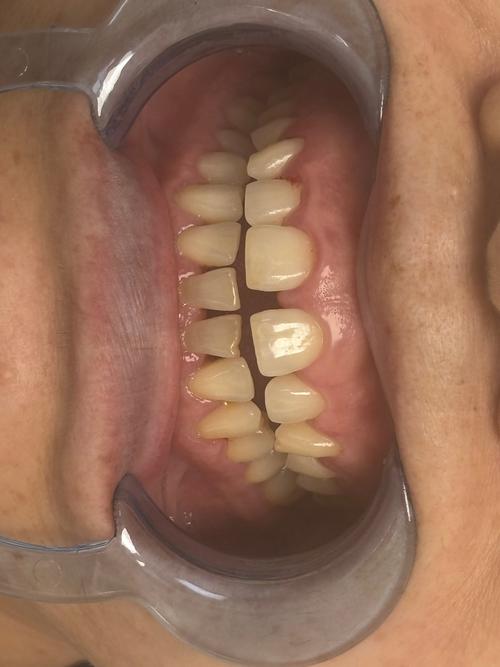

正畸(牙齿矫正)是通过专业矫治器对牙齿施加持续、轻柔的生物力,引导牙齿在牙槽骨内缓慢移动,最终实现排列整齐、咬合协调、面部美观的口腔治疗过程,这一过程中,牙齿的移动可能伴随牙缝的出现,而部分患者本身存在的磨牙问题(夜间磨牙症),也可能与正畸效果相互影响,了解正畸与牙缝、磨牙的关系,有助于患者更好地配合治疗,规避风险,达到理想效果。

牙缝在正畸中既是“结果”也可能是“过程”,其形成原因多样,需根据具体情况分析。

牙缝形成的原因

- 生理性间隙创造:多数情况下,正畸中出现的牙缝是治疗计划的必要环节,对于牙齿拥挤的患者,医生需通过扩大牙弓或拔除部分牙齿(如前磨牙)创造足够空间,让错位牙齿移动到正常位置,此时牙缝是“主动打开”的,属于正常现象,后续会通过邻牙移动逐步关闭。

- 牙周问题导致的病理性牙缝:部分患者本身存在牙周炎、牙龈萎缩等问题,牙槽骨吸收后牙齿失去支撑,出现牙缝,正畸过程中,牙齿移动可能加剧牙周组织负担,若未先控制牙周炎症,易导致牙缝扩大或牙齿松动。

- 矫治器附件影响:粘接托槽、带环等矫治器附件时,若位置不当,可能压迫牙龈或导致局部清洁困难,引发牙龈炎症,进而形成“黑三角”(牙间三角间隙),尤其多见于前牙区。